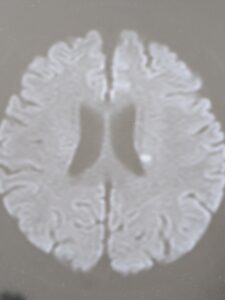

60代の女性の方です。

突然左足の力が入らないということで受診されました。

診察し、脳MRをとると

脳梗塞があり、総合病院に入院になりました。